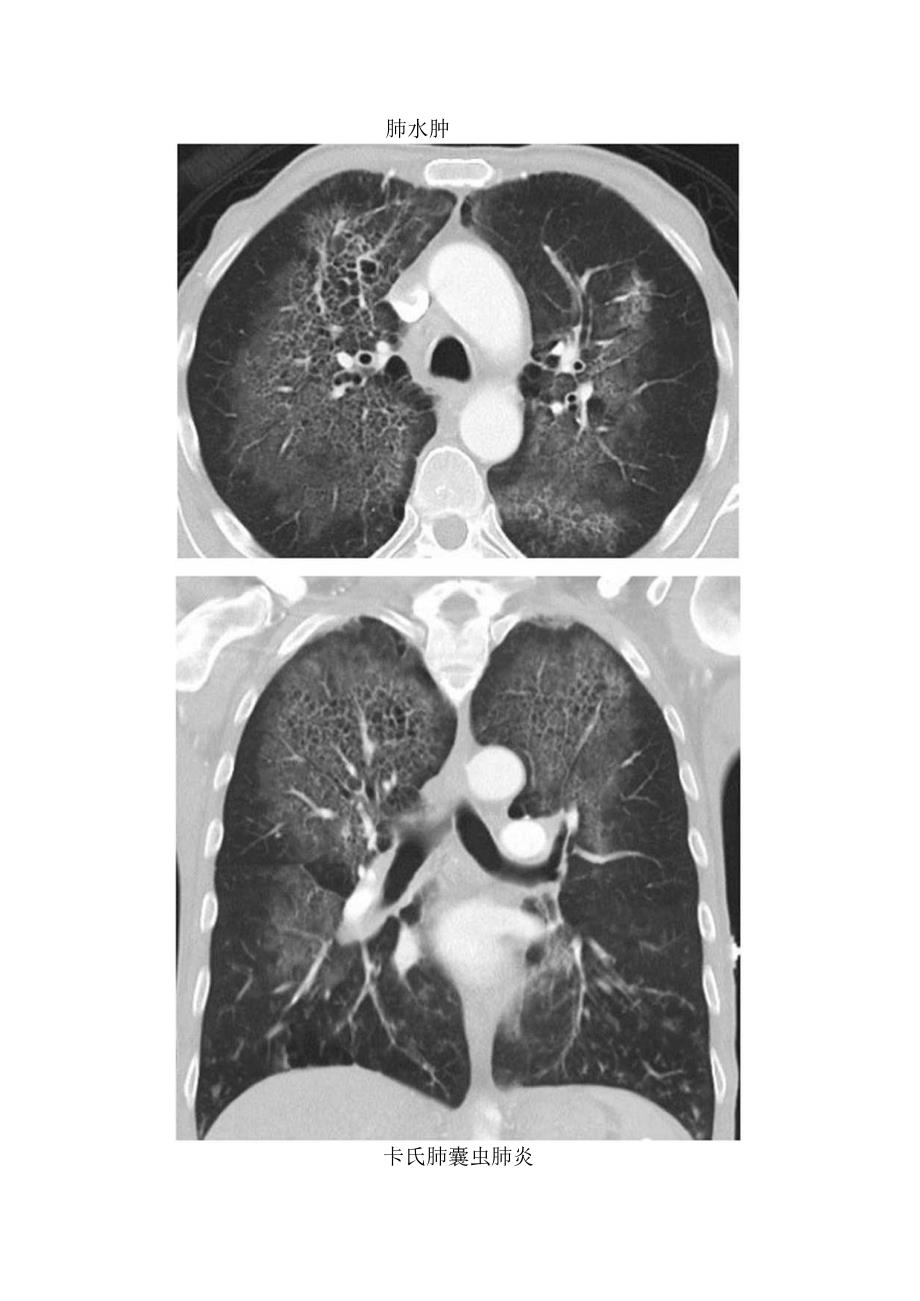

1、临床蝙蝠翼样肺部影临床表现、常见疾病及鉴别诊断蝙蝠翼征或蝶翼征蝙蝠翼样肺部影是指双侧肺门周围的阴影.通常在正位胸片上用来描述相关表现,也可指胸部CT上的表现。鉴别诊断:蝙蝠翼样肺部账可由以下原因引起:1、肺水肿(尤其是心源性);2、肺炎:吸入性肺炎、卡氏肺囊虫肺炎(PCP)、病毒性肺炎、脂质性肺炎;3、吸入性损伤:有毒气体、液体:4、肺泡蛋白沉积症;5、肺出血(如GOodPaStUre综合征):6、淋巴痛/白血病;7、支气管肺泡癌.肺水肿卡氏肺囊虫肺炎鉴别诊断常见流体静力性肺水肿肺炎不常见 肺损伤 肺出血罕见(但重要) 肺泡蛋白沉着症I-信息鉴别诊断要点 经典描述于正位X线胸片,尽管也见于CT

3、界不清的小叶中心型结王,尤其在罕见诊断的有用线索肺泡蛋白沉着症C多数病例为特发性肺实质充满蛋白质样物质;间质增厚CHRCT上表现为铺路石征急性间质性肺炎特发性疾病,导致弥漫性肺泡受损C伴有病毒前驱症状乂称HammanRich综合征(左)正位X线胸片示急性肺水肿的典型X线特征.表现为蝙蝠翼样实变。病因为急性充血性左侧心力衰竭(右)正位X线胸片示双侧中央性肺实变,以左侧为甚。经证实该免疫受损患者患有(左)正位X线片示吸食可K因所致的双侧中央型肺水肿,呈蝙蛆翼样分布=(右)淹遨史患者。正位X线片示双侧中央型肺实变=o肺部损伤导致非心源性肺水肿。注意其与其他原因所致的中央型肺实变的表现相似,应重视临床病史(左)横断位增强CT示书格纳肉芽肿病的一种变异表现,双侧肺出血以蟾蝠翼样分布同时注意左肺下叶铺路石征(右)横断位平扫CT示双侧中央型致密实变向I。此为肺出血患者,血液从气管插管内吸出,是诊断的重:要(左)横断位平扫CT示双肺磨玻璃影伴间质性间隔增厚,称为铺路石征。注意其以中央性分布为主征象无特异性,但在适当的临床表现下,其符合肺泡蛋白沉着症表现(右)冠状位平扫CT示双侧广泛磨玻璃影巨,外周正常,呈地图样。此为典型的急性间质性肺炎表现